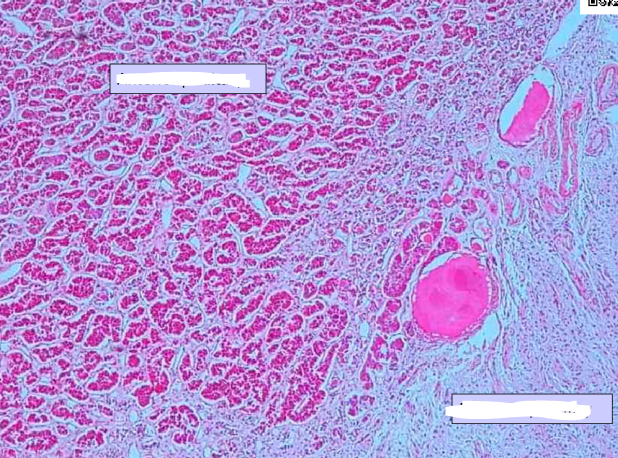

name the cells at the arrows